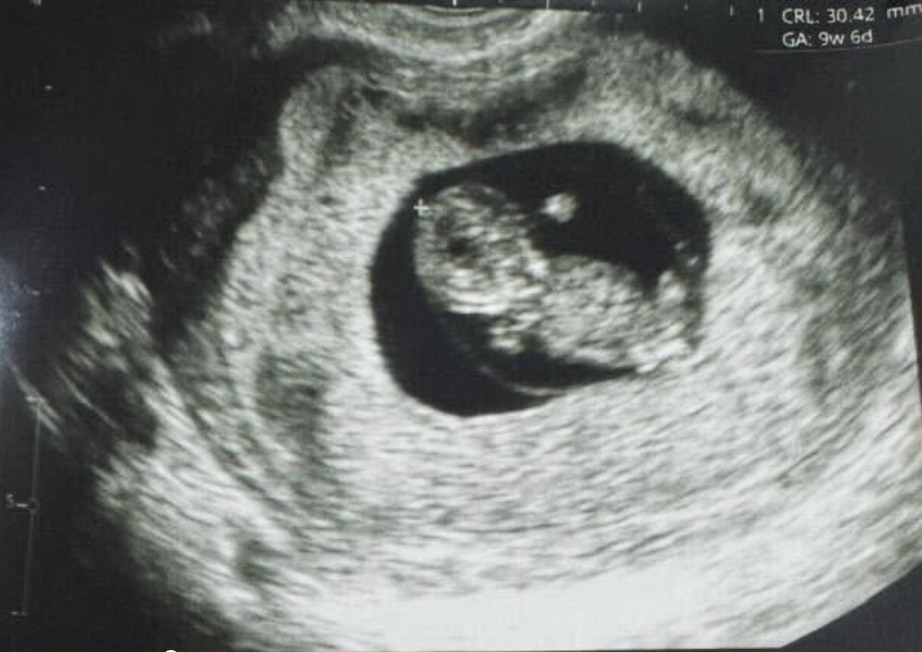

全球首例:使用誘導(dǎo)多能干細(xì)胞體外成熟卵子技術(shù),成功產(chǎn)下一名嬰兒

紐約(?BUSINESS WIRE?)致力于推動女性健康治療方案發(fā)展的生物技術(shù)公司Gameto與2024年12月16日宣布,該公司利用 Fertilo 實現(xiàn)了全球首例活產(chǎn)。此次分娩在秘魯利馬的圣伊莎貝爾診所進(jìn)行。